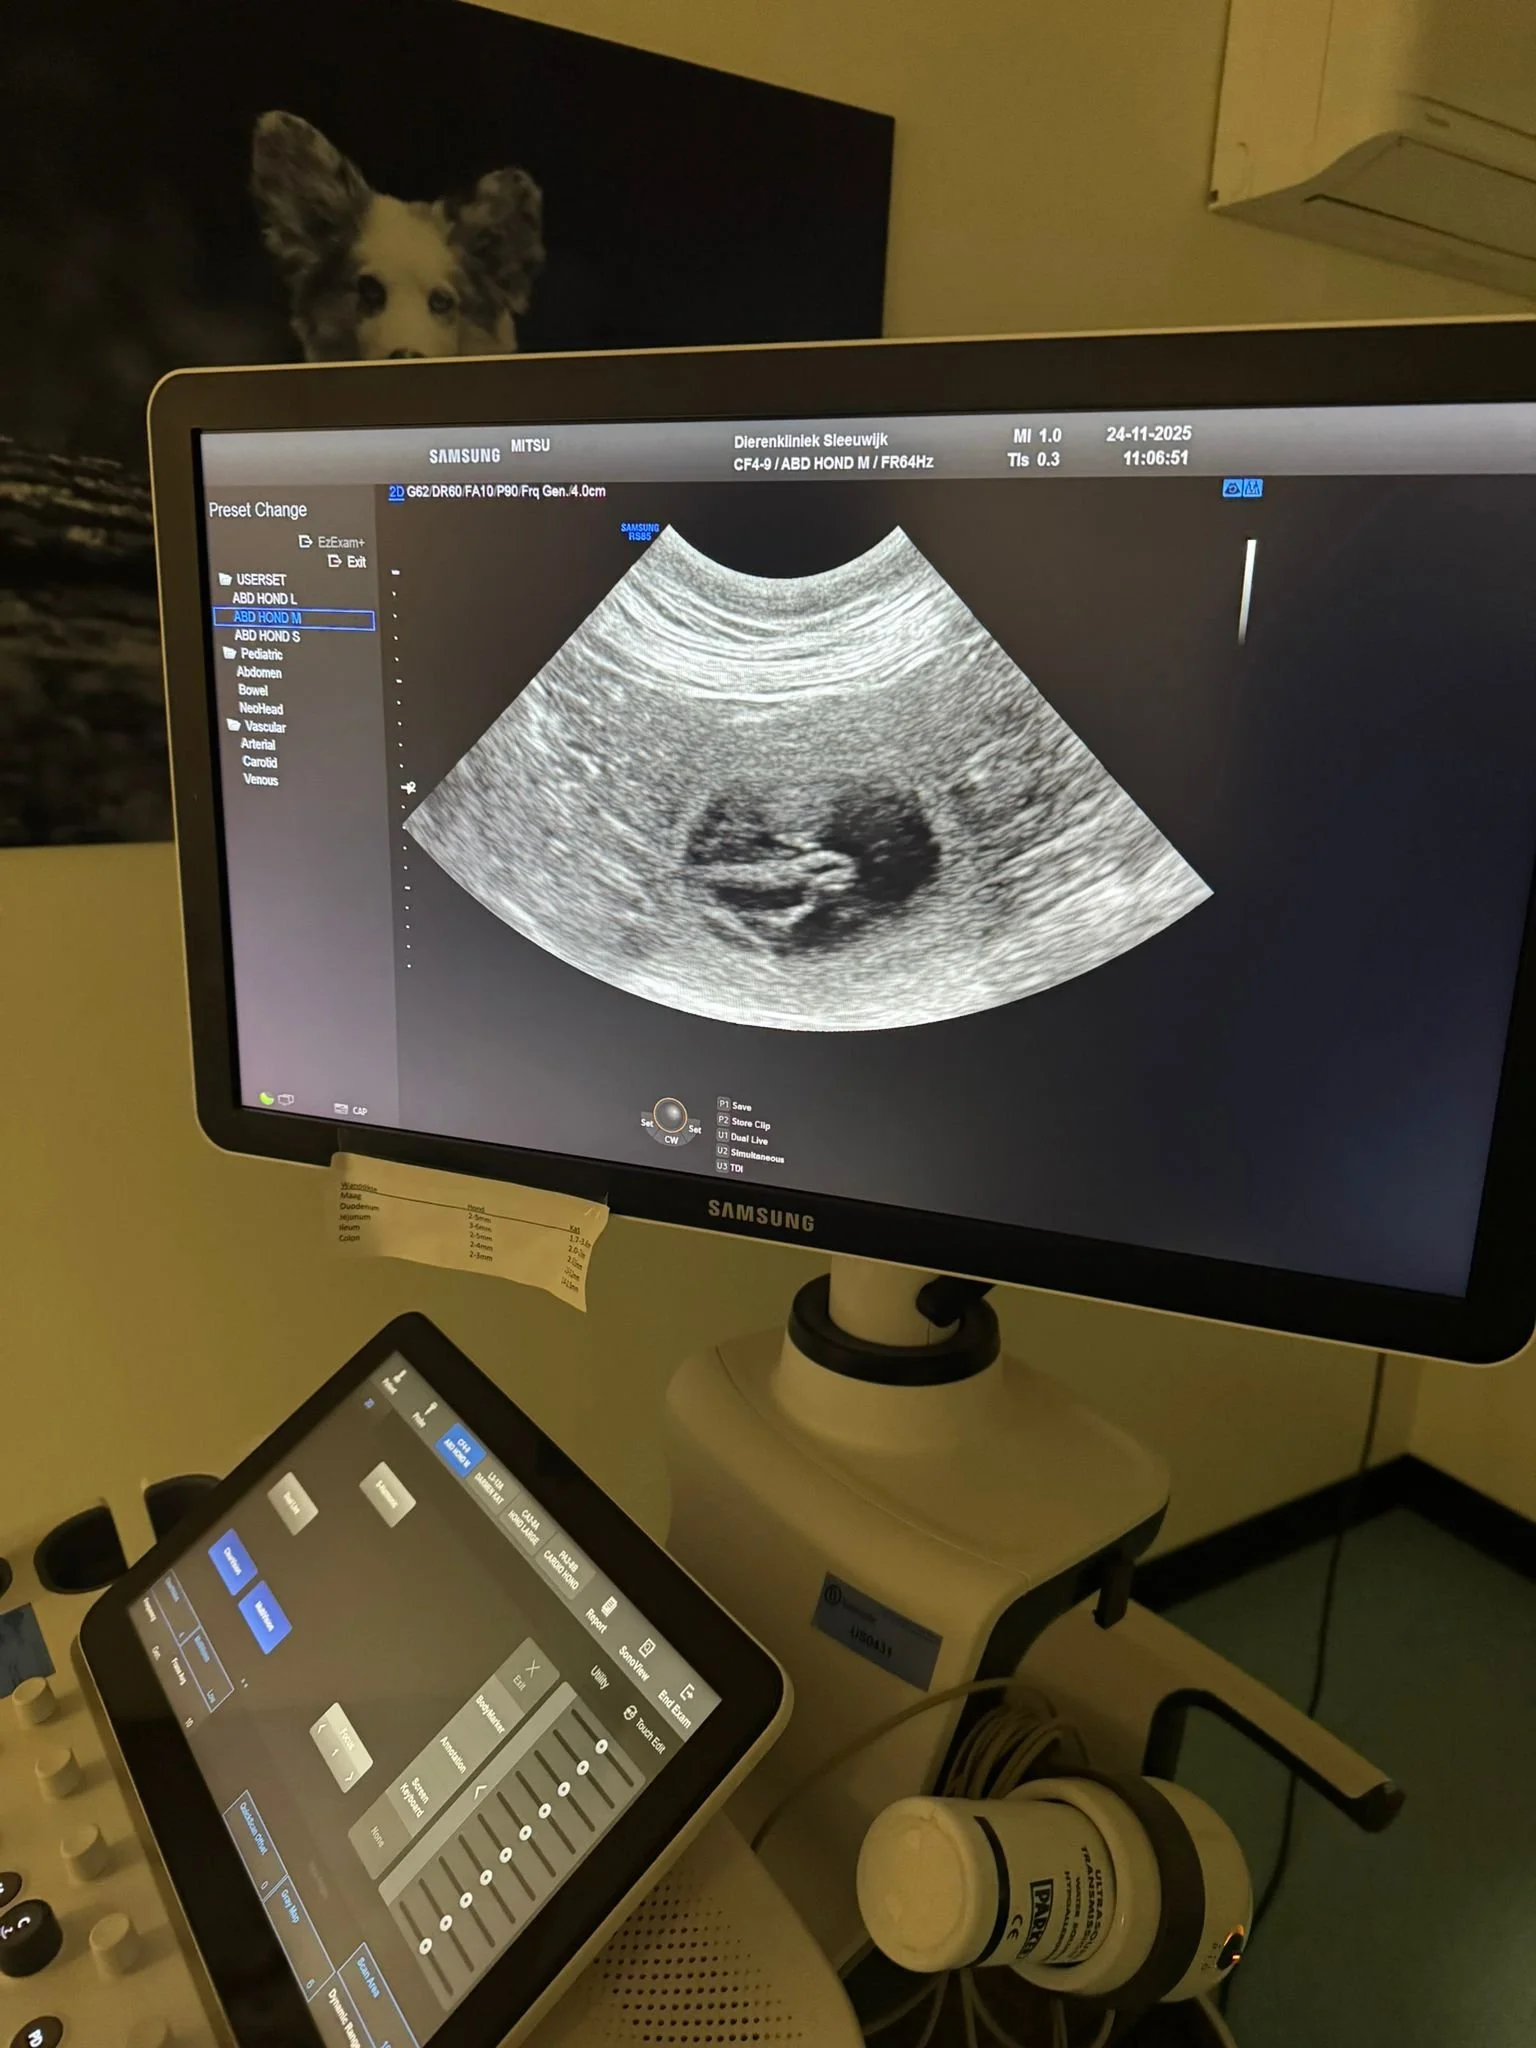

Mitsu is drachtig! 24 nov Geschreven door Raisa Ramkhelawan 24 november: Mitsu is drachtig! We hebben een echo gehad en Mitsu krijgt minstens 5 pups. We verwachten de pups rond 2e kerstdag. Heb je interesse in een pup, stuur ons dan een mailtje of vul ons contactformulier in! Raisa Ramkhelawan